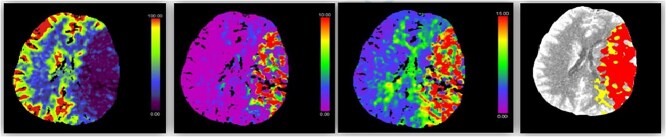

Malignant Middle cerebral artery (MCA) infarction is characterized by rapid neurological deterioration due to cerebral edema. Spasticity, a common sequela of stroke, typically occurs days to weeks after the initial event. However, an acute onset of spasticity at presentation is extremely rare. We report a case of a 40-year-old male patient who presented with spasticity accompanied by aphasia and decreased consciousness. Left MCA occlusion was demonstrated on Computed tomography (CT) angiography. Cerebral edema developed rapidly, requiring decompressive hemicraniectomy (DH). The patient was a known smoker with androgenic anabolic steroid use. This case represents a rare presentation of malignant MCA infarction with acute spasticity and adds a unique aspect to the clinical spectrum of stroke presentation. This case emphasizes the need for awareness of atypical stroke presentation and the potential role of anabolic steroids in stroke risk.